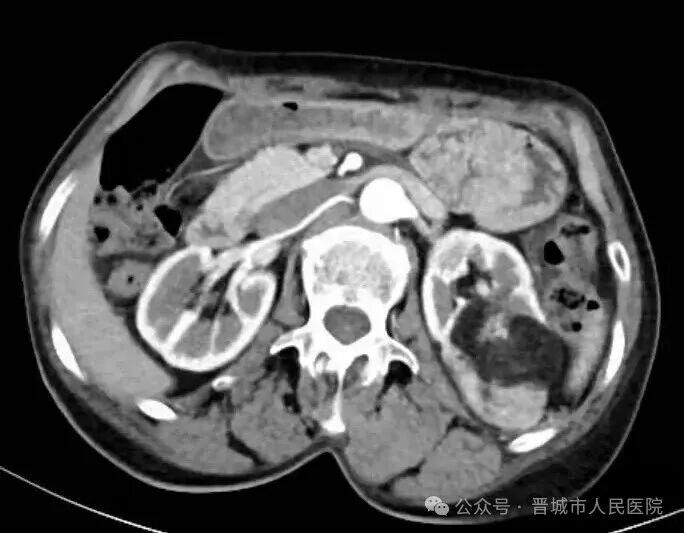

据了解,患者因体检发现左肾占位20余天入院,外院检查提示左肾肿物大小约45*55*98mm,接近十公分的肿瘤体积给治疗带来了极大挑战。更为棘手的是,患者年事已高,体质薄弱且营养状况欠佳,腹壁肌肉薄弱导致手术戳卡固定困难,传统腹腔镜手术操作空间受限、难度极高,而患者及家属保肾意愿十分强烈。

手术过程中,机器人系统的多自由度机械臂展现出独特优势,可灵活模拟人手动作,突破传统腹腔镜的操作角度限制,在狭小的术野内实现精细分离与操作。配合高清3D视野系统,术者能清晰辨识肾脏血管与肿瘤边界,精准把控手术节奏,有效规避血管损伤风险,为肿瘤完整切除和肾脏功能保留奠定了基础。